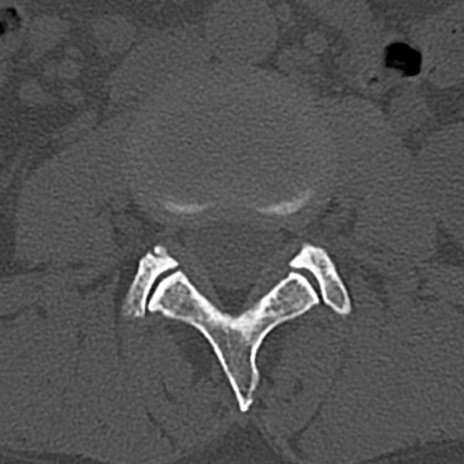

腰椎CT

横断像と矢状断像